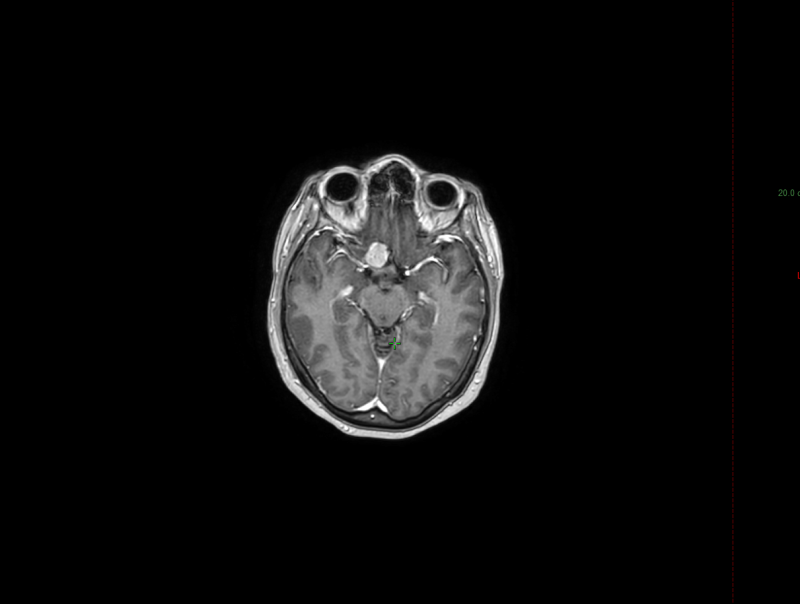

Пациентка А., 45 лет, обратилась в нашу организацию с диагнозом «Менингиомы бугорка турецкого седла справа» – опухоли, которая располагается в области перекреста зрительных нервов. Эта локализация представляет особую сложность из-за близости к зрительным путям и высокого риска потери зрения при неправильном подходе к лечению.